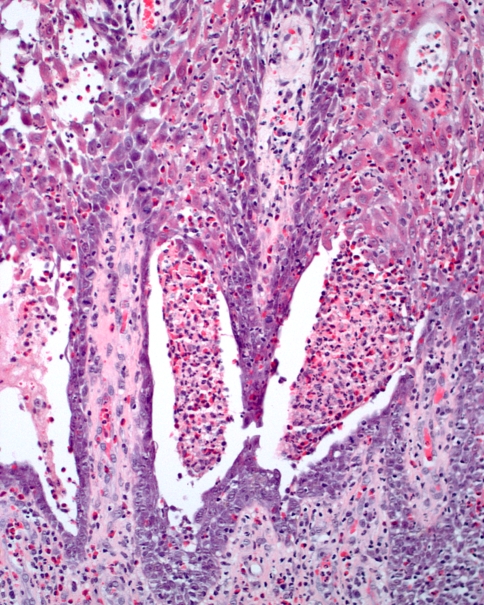

The microscopic features are quite characteristic, consisting of an intense infiltrate of eosinophils into the epithelium, resulting in intraepithelial abscess formation (Fig. 8). The spinous cells often demonstrate intercellular edema with acantholysis. In some cases, both intraepithelial and subepithelial abscess formation will be observed. A heavy mixed inflammatory cell infiltrate with numerous eosinophils is also present in the lamina propria.

Fig. 8.

Pyostomatitis vegetans. This medium power photomicrograph shows an intraepithelial abscess of eosinophils and neutrophils